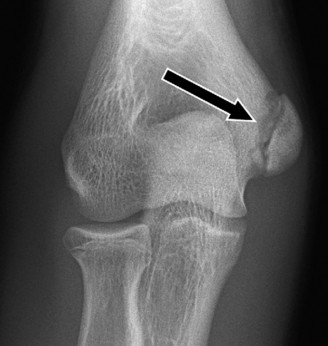

Treat a patient with infected total shoulder arthroplasty? CASE 21 A 70-year-old, right-hand-dominant female presents to clinic complaining of 4 years of gradually worsening chronic right shoulder pain and stiffness. She says the pain is worse at night and with any range of motion, denies a history of trauma, pain in other extremities, or numbness or tingling of the right upper extremity. She notes that her mother suffered from rheumatoid arthritis that affected her shoulder. Physical examination reveals decreased muscle bulk over the right supra- and infraspinatus fossae compared to the contralateral side, limited active and passive ROM, marked weakness with external rotation, and 4+/5 strength with shoulder abduction. X-rays of the right shoulder are shown in Figures 2–58 and 2–59.

Figure 2–58

Figure 2–59

What is the most likely diagnosis?

- Rotator cuff tear arthropathy

The correct answer is (C). Rotator cuff tear arthropathy consists of a combination of rotator cuff insufficiency, glenohumeral joint degenerative changes, and superior humeral head migration. It is more common in women and also more often found on the dominant side. The patient’s clinical examination with weakened external

rotation and muscle atrophy signaling incompetent supra- and infraspinatus muscles point to rotator cuff insufficiency, and her plain films reveal narrowed glenohumeral joint space as well as superior migration of the humeral head. Choice D is incorrect because, while radiographs would show narrowing of the glenohumeral joint space, they would also likely show numerous osteophytes and posterior wear of the glenoid. Choice B is incorrect because, while adhesive capsulitis does present as decreased active and passive range of motion, the patient’s constellation of symptoms pointing towards rotator cuff insufficiency along with the radiographs make cuff tear arthropathy the more likely choice. Finally, Choice A is incorrect because even though she has a positive family history of rheumatoid arthritis, it is less likely to present only in a single joint. Also, rheumatoid arthritis on radiography appears more as an erosive process without the characteristic superior migration of the humeral head.

Which of the patient’s radiographic findings is most indicative of chronic rotator cuff insufficiency?

- Superior migration of the humeral head

The correct answer is (A). Superior migration of the humeral head would be most indicative of chronic rotator cuff insufficiency associated with cuff tear arthropathy, as it is a direct result of the inability of the rotator cuff tendons to help maintain the humerus in its normal position. Acetabularization of the undersurface of the acromion is commonly associated with superior migration of the humeral head found in rotator cuff tear arthropathy, and can be assessed using the Hamada classification, which is based on measurements of the acromiohumeral interval on radiography (Table 2–8). Choices B and C are incorrect because, while narrowed glenohumeral joint space and subchondral sclerosis are associated with rotator cuff arthropathy on radiographs, they indicate degenerative joint changes rather than chronic rotator cuff insufficiency. Choice D is incorrect because it is not a specific sign of rotator cuff arthropathy.